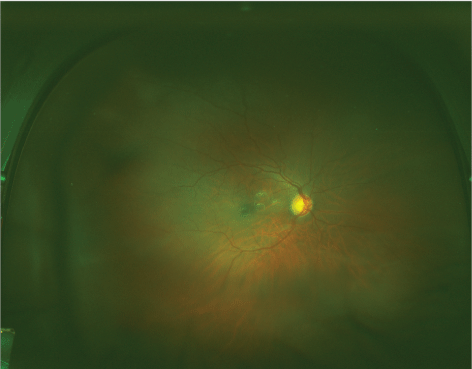

After 10 days of treatment, Patient's ulcer was slowly improved. On slit lamp exam, 10% hypopyon was seen and 1+ chemosis (Table 3 and Table 4). She was discharged with topical tobramycin and topical amphotericin to continue 4 times a day and Isavuconazole 372 mg daily to continue for 6 weeks. She was followed up by ophthalmology at outpatient clinic. At 3 month follow up, eye exam was as follows and she was microbiologically cured. However, since in the delay of seeking medical care initially, corneal scarring was observed and corneal grafting was required to restore vision (Figure 2, Figure 3).

Figure 3: No significant abnormality present on funduscopic exam. View Figure 3